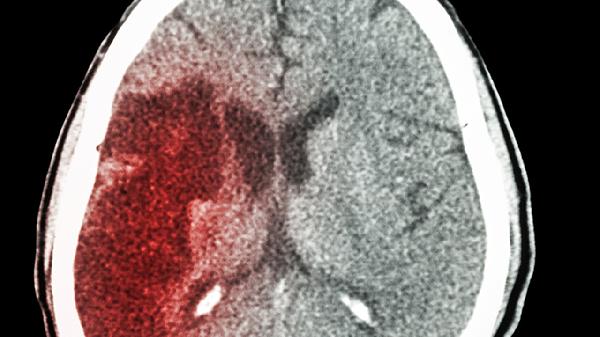

脑梗这个"沉默杀手"的诱因清单可能要刷新了!很多人以为肥肉是罪魁祸首,但最新研究发现,真正危险的竟是那些藏在日常饮食中的"伪装者"。它们看似无害,却可能在血管里悄悄埋下隐患。